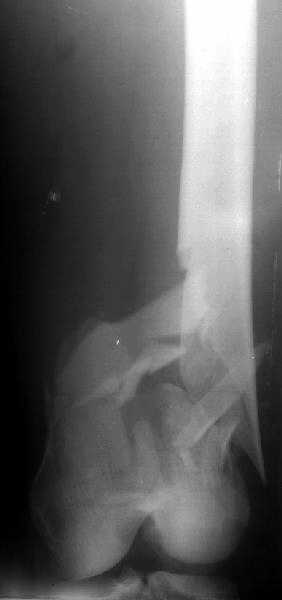

de> you think you are using antigrade nails for some very low

de> fractures including some intercondylar fractures.

Exactly. It seems the option looks underestimated.

I attached an example of C2 fracture with result of the same technique in 5 months.